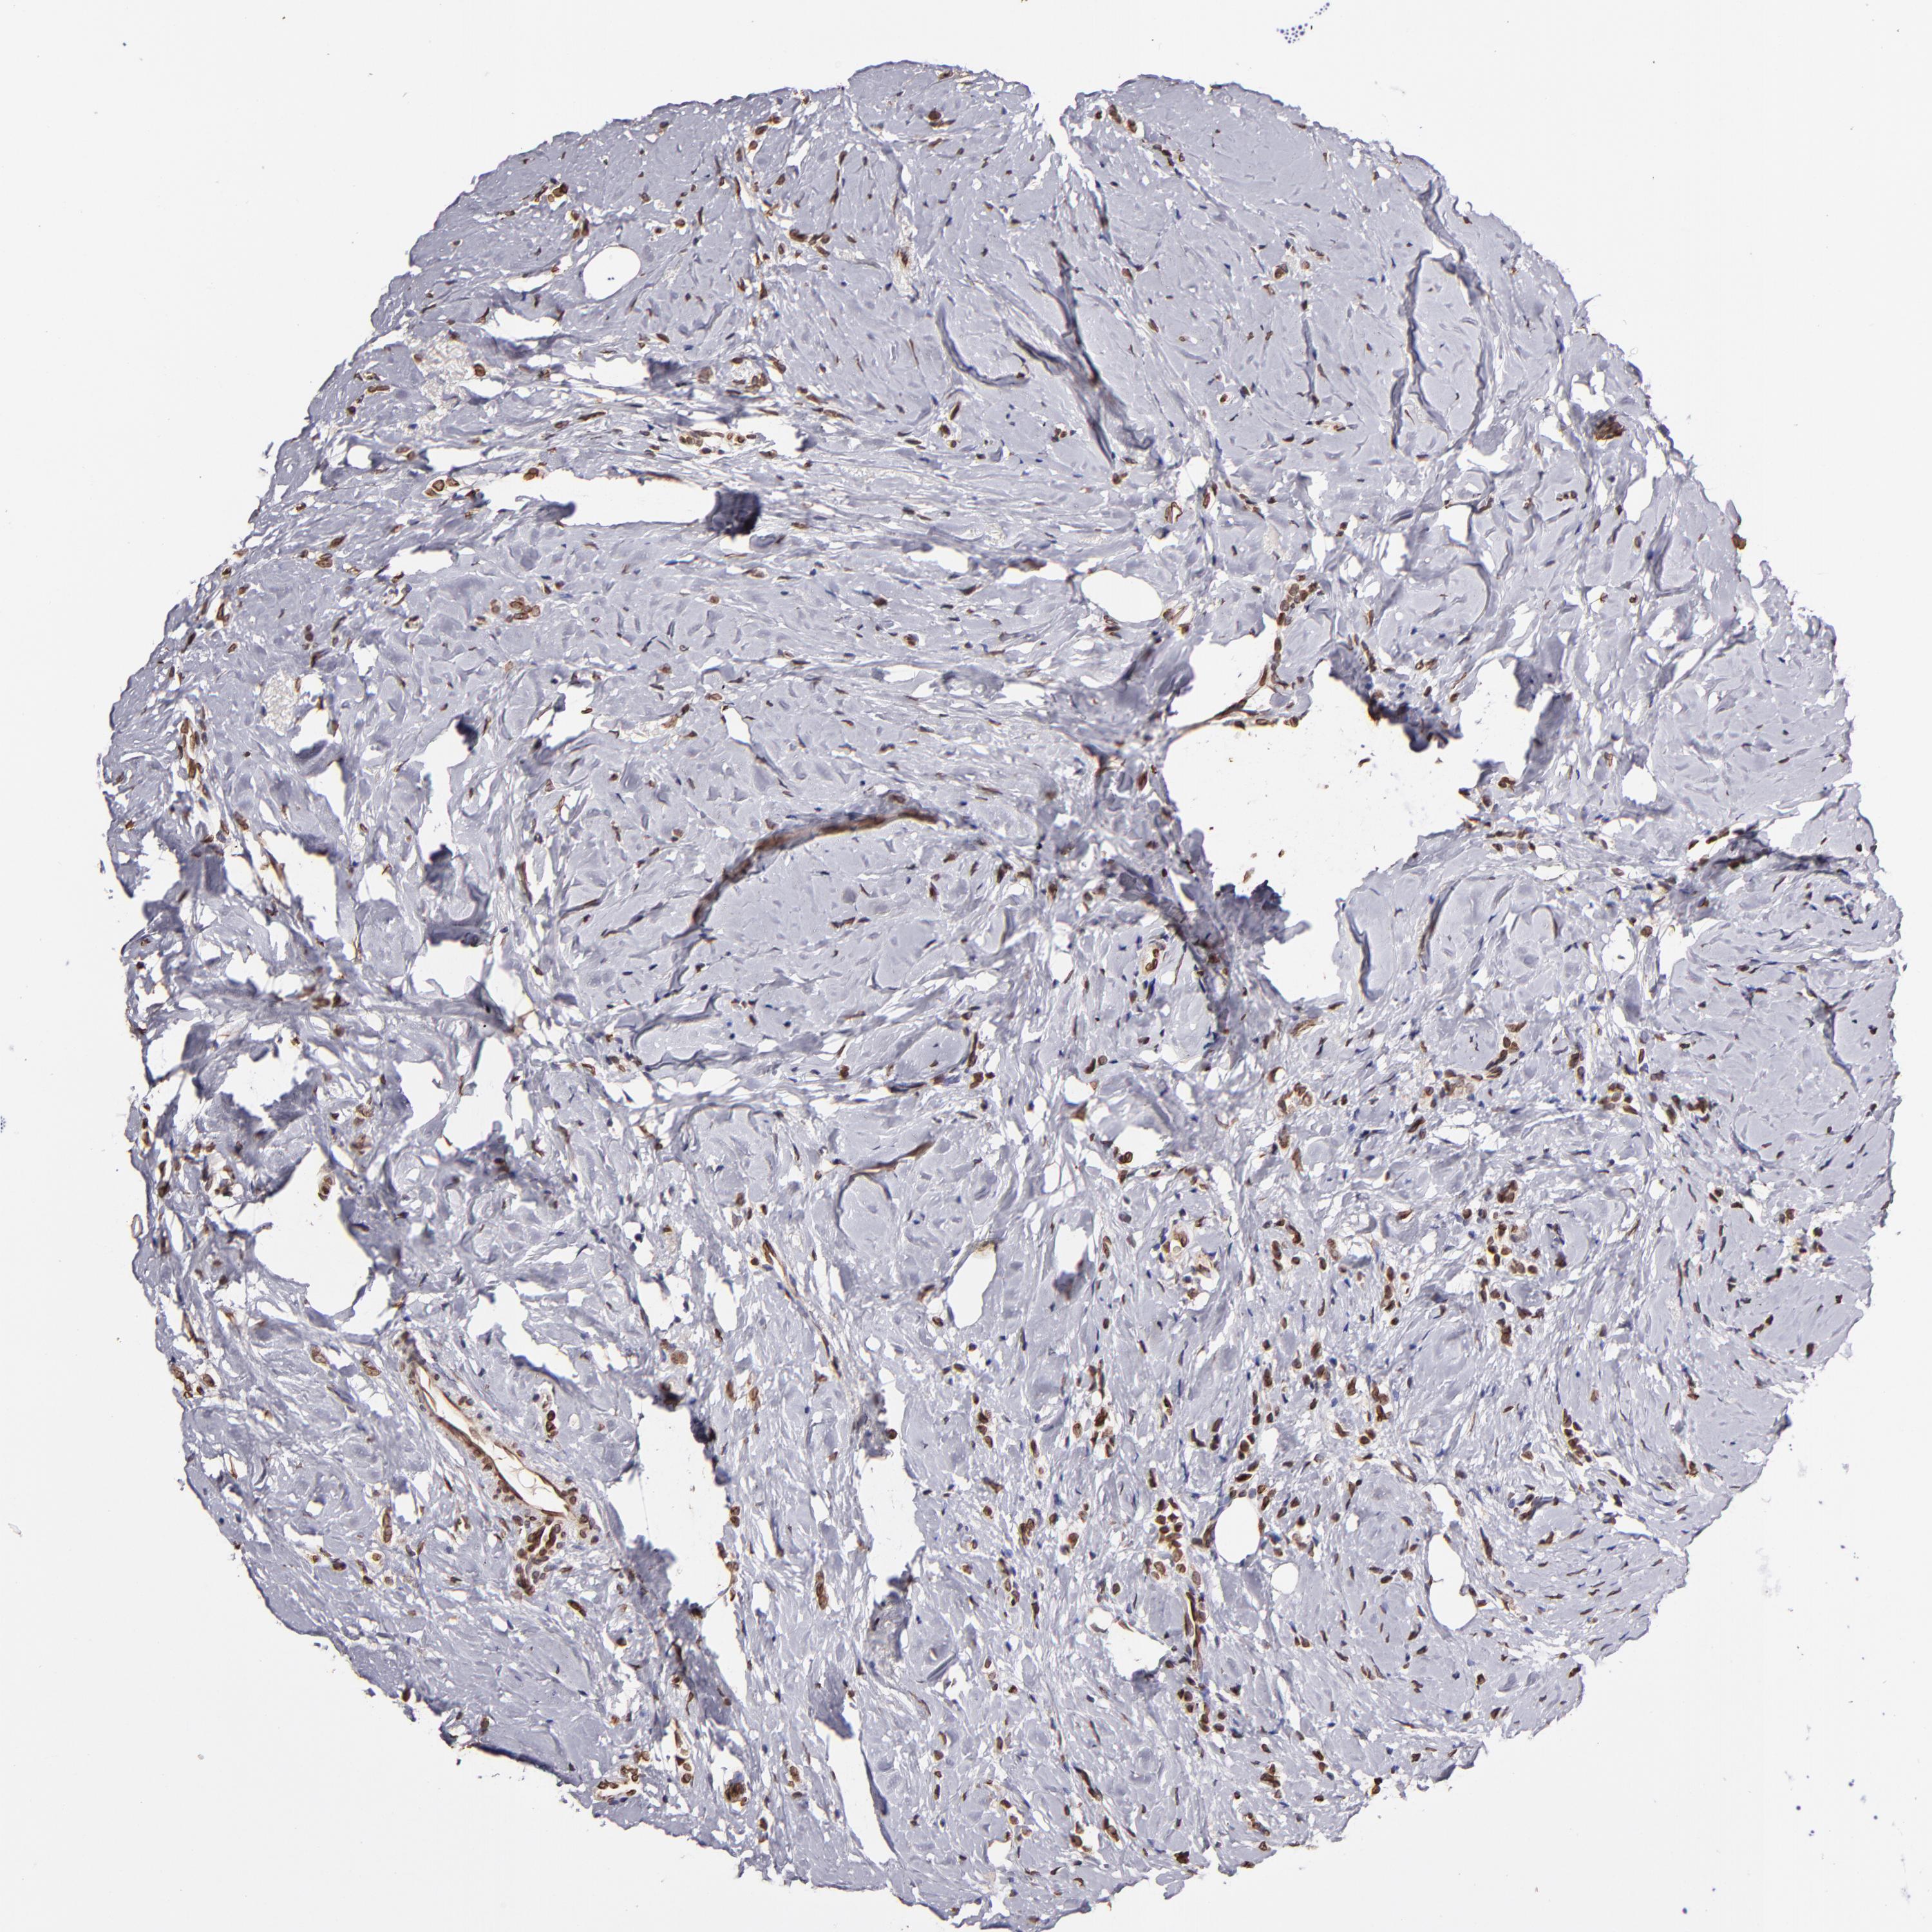

BRCA TCGA BRCA VALIDATION PROTEIN EXPRESSION